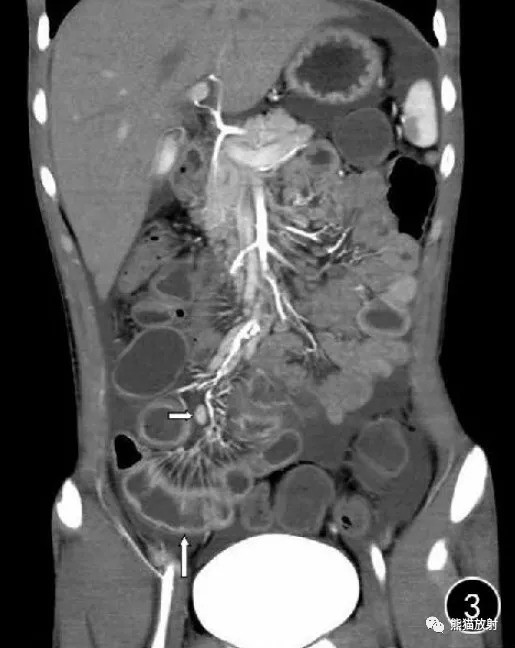

[深刻解读] 肠壁积气的征象、原因和意义(建议